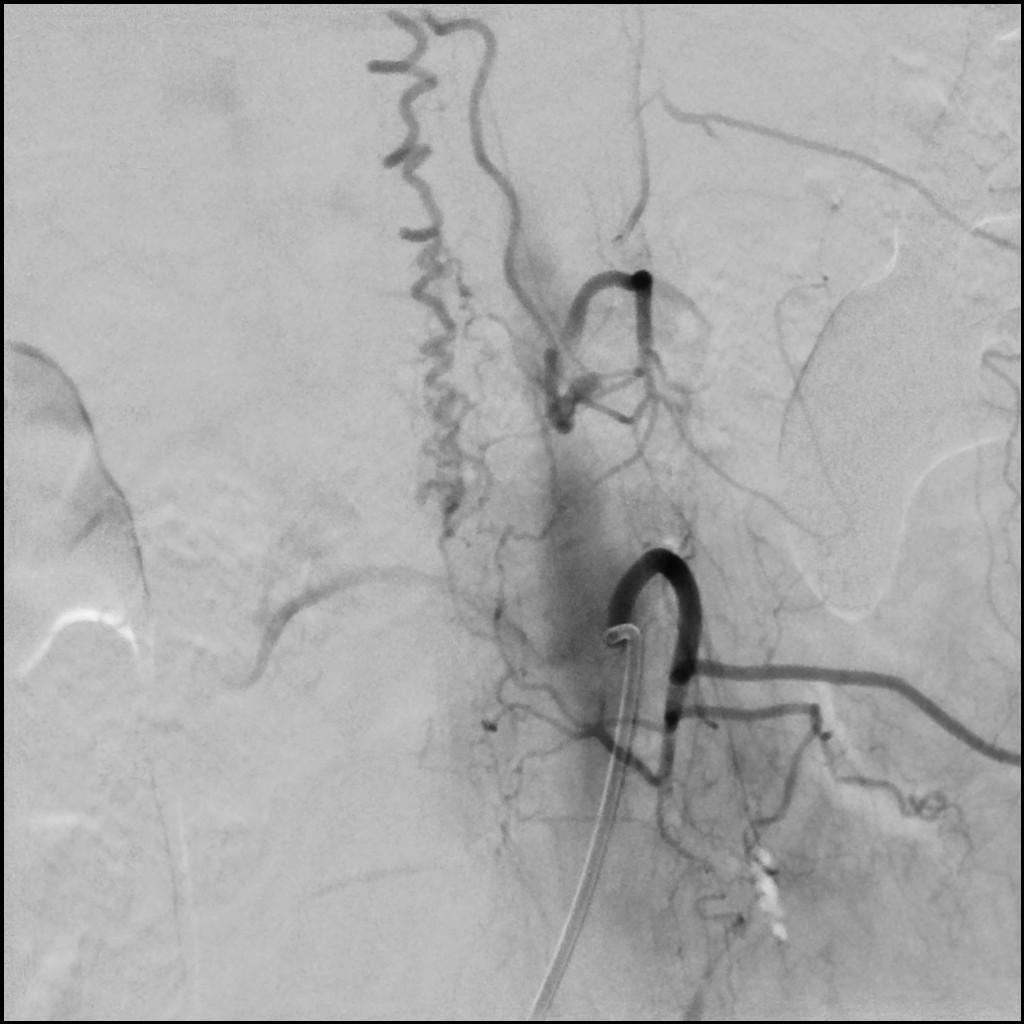

Diagnóstico final: FISTULA DURAL

Etiología: Malformación vascular